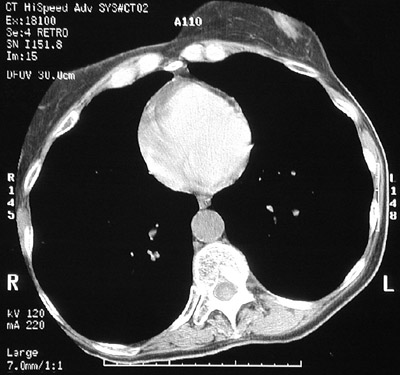

| The chest CT scan view above in "bone window" reveals marked lucency in a patient with severe centrilobular emphysema. Note how the heart is dwarfed by the increased total lung capacity. The view below of this patient is in "lung window" setting for CT scanning. |